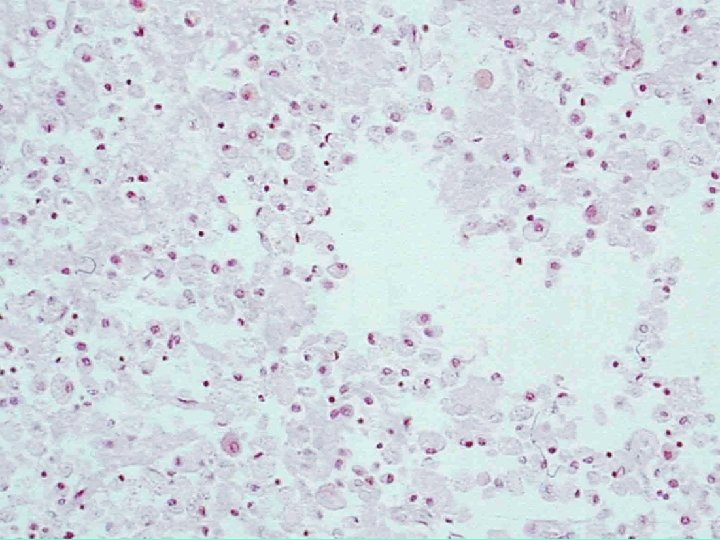

Caseous necrosis • Soft and white: like cream cheese • Amorphous eosinophilic mass, loss of tissue architecture • Associated with granulomatous inflammation(reaction) in Tuberculosis